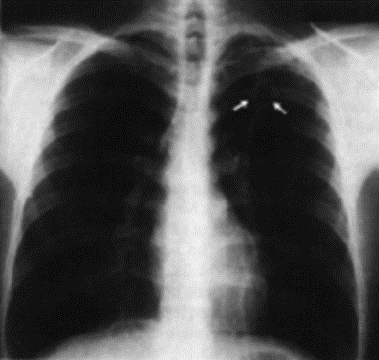

1.2.1 Radiografia (tomografia, broncografia)

Metodo diagnostico prevalente, eventualmente completato con tomogramma delle parti dubbiose o broncografia (a contrasto).

Non specifici, normalmente si scopre per caso in una radiografia polmonare. Si distinguono forme croniche e acute.